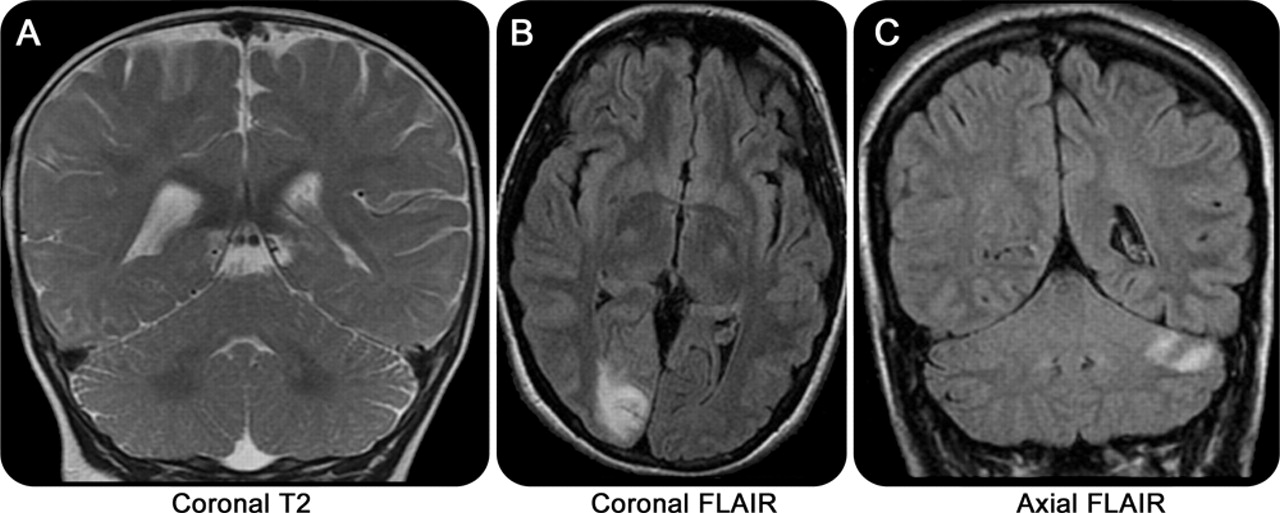

进步枕和丘脑核磁共振成像病变,包括增加皮质diffusion-weighted MRI信号强度,通常观察到的早发性和青少年Alpers。18,20.,21增加信号强度在小脑也很常见。MRI异常可以发现造成可以迅速进步,18,22,23但是MRI也可以是正常的(图3A)。灰质神经元损失与活性astrocytosis Alpers综合症的病理相关。15

(一)正常冠状T2图像的10个月大的婴儿Alpers综合症。(B)轴向fluid-attenuated反转恢复(天赋)的一名15岁女孩肌病,认知能力下降,癫痫,共济失调显示左枕叶梗死。19岁的女人(C)冠天赋与药物抗癫痫和类似中风事件显示了左小脑梗塞。POLG =γ-catalytic线粒体DNA聚合酶亚基。

成像结果变量。MRI异常包括广义脑萎缩、选择性小脑萎缩,与枕叶和多焦点的T2信号异常偏爱(图3B)。